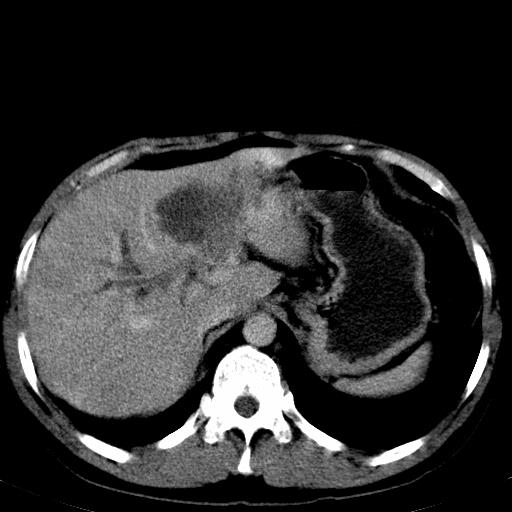

患者上腹部疼痛一月余,伴巩膜黄染;

实事求是的说,强化效果很一般,重点部位应重点观察,但有一点可以明确:肝门部胆管细胞癌。

考虑肝左叶胆管细胞癌侵犯肝门区并肝内胆管及肝总管扩张。

肝左叶肿块清度增强,所在的叶胆管扩张。考虑胆管细胞癌。